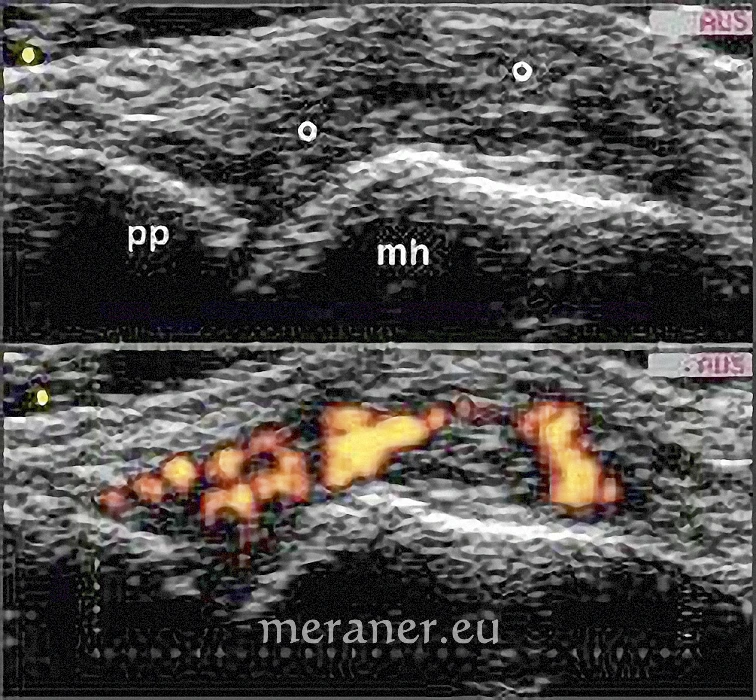

Ultraschallbilder eines Gelenks zwischen Mittelhand („mh“) – und Fingerknochen (proximale Phalanx, „pp“). Im oberen Bild sieht man das aufgetriebene, mit gräulich erscheinendem, entzündlichem Material (durch ° markiert) ausgefüllte Gelenk, im unteren Ausschnitt eine Darstellung der im Gelenk befindlichen Entzündung mittels Power-Doppler-Modus. Quelle: P. Matzneller